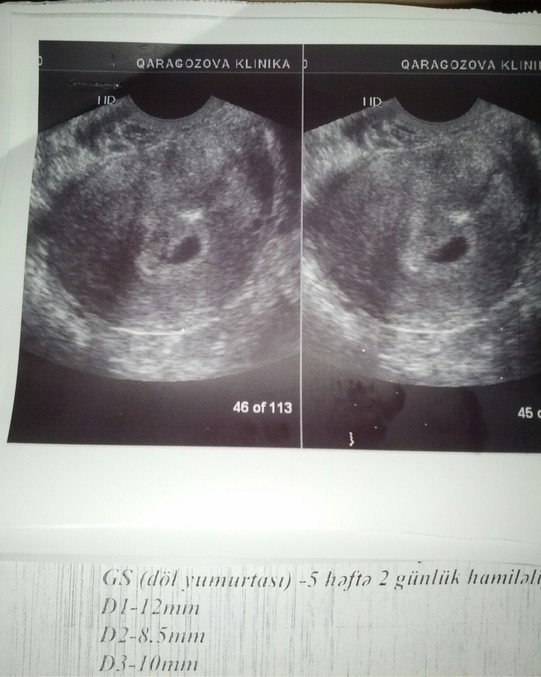

Сходила на узи.нам поставили срок по эмбрион у 5 недель и 4 дня. сердечко стучит. получается во время операции я была Б ?????????? Короче врач не понимает что это???? Богом посланное чудо. тонуса нет.впрочем все в шоке.я забеременела даже без месячных.если считать лапару 1 днем цикла у меня срок 3 недели 4 дня,а эмбрион соответствует 5 неделям и 4 дня.не понимает никто )))) Девочки верьте в Бога!! Чудеса на самом деле случаются

Моя гиня и врачи ничего не понимают ))))) во время операции у меня была киста в правом яичнике то есть фоллик перерос в кисту,а это беременность слева фоллик лопнул получается после операция была овуляция но почему эмбрион соответствует 5 неделям???? Врач сказала это от Бога и эту Б она не поняла)))))